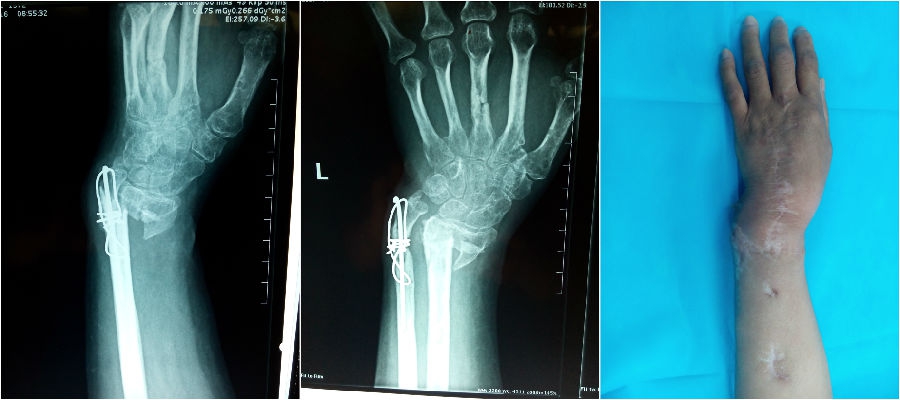

为了恢复手腕部功能,进行功能重建,高女士于2017年2月再次入住手显微外科一病区,通过三维CT检查发现,桡骨远端骨折依旧没有愈合,远端向掌侧移位,桡腕关节活动受限,桡骨远端关节面破坏严重(图1)。

图1.

这种情况下,单纯进行植骨内固定无法改善患者手腕功能,而且高女士从事的工作对手腕的旋转功能要求较高,手显微外科一病区宫可同主任根据CTA检查结果制定了截取患者本人对侧带有膝下外侧动静脉血管的腓骨头,移植到腕部,代替受损的桡骨远端,进而达到重建桡腕关节的治疗方案,这样就可以恢复其手腕部的大部分功能。手术前在影像技术的指导下定位膝下外侧动脉,测量桡骨缺损长度,于对侧小腿切取约5 cm腓骨头,保留了膝下外侧动静脉血管蒂、神经、皮岛(便于观察移植腓骨头的血运),移植到左手桡骨部位,对腓骨与桡骨、桡腕关节分别进行内固定,吻合了移植的血管、神经、皮岛(图2),术后10天移植的皮岛成活,高女士顺利出院,正在进行康复锻炼中(图3)。据悉,该高难度手术在天津市属首例,国内罕见开展。

图2

图3